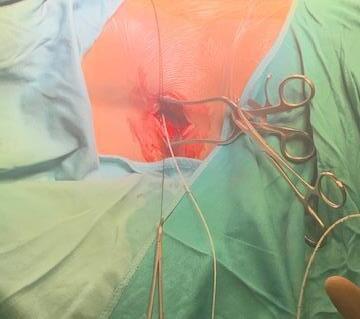

Adductor Longus L2, L3

Vastus Lateralis L3,L4

Tibialis Anterior L4, L5

Peroneus longus L5, S1

Gastrocnemius S1, S2

Abductor hallucis S1, S2

Sphincter S2